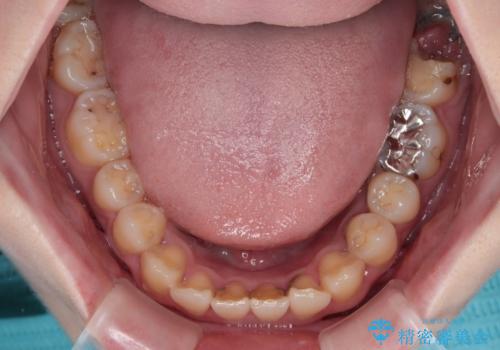

- 過去の歯医者通いの恐怖から虫歯を放置してきたものの、一大決心して来院された患者様です。

神経組織の失活している歯や歯根だけが残っている歯などがあり、全体的に歯石も多く付着している状態でした。

まずは歯石除去とブラッシング方法などの衛生指導を徹底的に行って口腔内環境を改善し、汚れの溜まりやすくなっている親知らずは全て抜去することとしました。

その後、歯根だけとなっている歯はインプラントに、神経組織の失活している歯は根管治療を行い、いずれもオールセラミッククラウンにて補綴治療を行うこととしました。